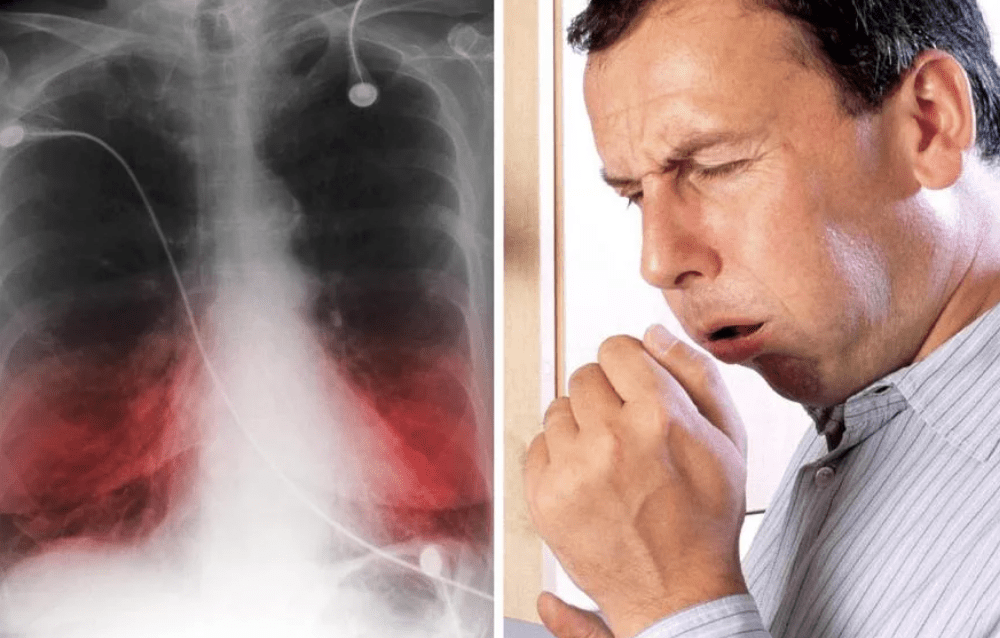

При ОРЗ, ОРВИ, гриппе поражаются альвеолы. Это части легкого, в которых происходит обмен газов между кровью и воздухом. Заболеванию, в зависимости от тяжести, подвергаются одна или две альвеолы и окружающие ткани. В итоге нарушается естественное дыхание, вентиляция, скапливается мокрота.

В этой среде быстро и легко размножаются бактерии, которые провоцируют начало воспалительного процесса в отдельных частях легких. Начинается пневмония.

Если она вызвана COVID-19, то процесс воспаления проходит по-другому. Причиной становятся не бактерии, а вирус. Он нарушает привычную работу альвеол. В них накапливается не только жидкость, но и отмершие клетки. При таком типе воспаления поражаются уже все легкие, а не их части.

При обычной пневмонии лечение основывается на приеме антибиотиков. При воспалении легких, вызванном коронавирусной инфекцией, надо в первую очередь справиться с вирусом SARS-CoV-2. Связь COVID-19 с воспалением легких прослеживается, но это не одно и то же.